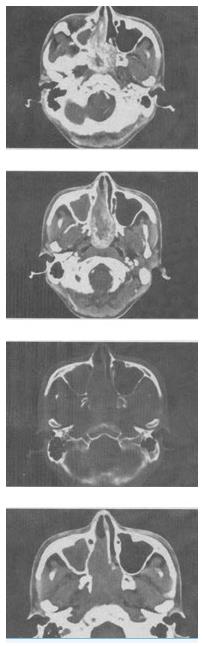

- 单项选择题 男,20岁,头痛、鼻塞、鼻出血,CT如图所示,最可能的诊断是()。

- C